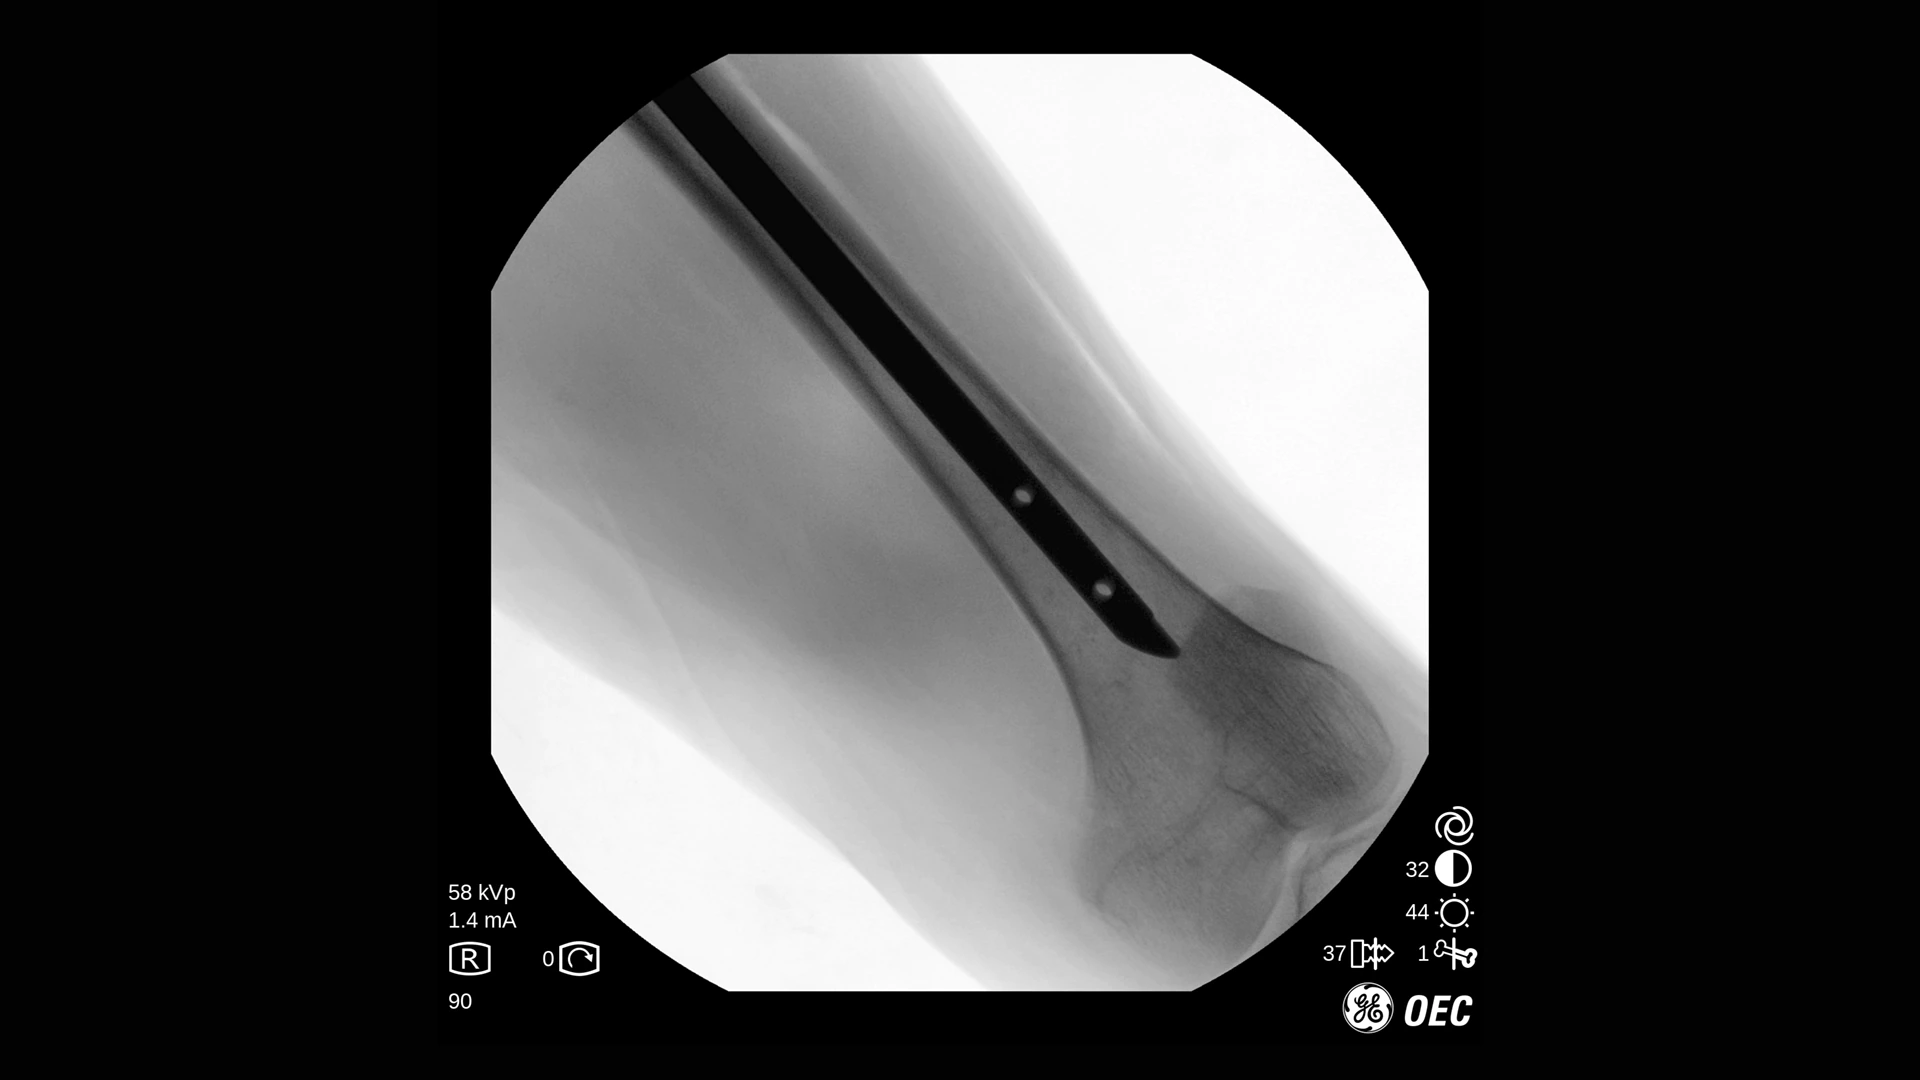

GE Healthcare OEC One CFD относится к классу мобильных рентгеновских аппаратов с С-образной дугой, в которых все ключевые узлы — излучатель, детектор, монитор и панель управления — объединены в единую компактную конструкцию. КМОП-плоскопанельный детектор и фирменная цепочка обработки Clear View обеспечивают высокую детализацию изображения в широком спектре клинических задач: от рутинных травматолого-ортопедических вмешательств до эндоваскулярных процедур и сложной спинальной хирургии. Интеллектуальные алгоритмы подавления помех от металлоконструкций, автоматической оптимизации окна и уровня, а также режимы увеличения позволяют уверенно визуализировать мелкие структуры, проводники и импланты без существенного роста дозовой нагрузки.

- Интеллектуальные алгоритмы обработки изображения (в том числе подавление помех от металлоконструкций и автоматический выбор окна/уровня).

- Функции Live Zoom и работа с последней рентгеноскопической последовательностью для снижения количества повторных экспозиций.

- Специализированные клинические профили для ортопедии, спинальной хирургии, общей хирургии, урологии, сосудистых и болевых процедур.